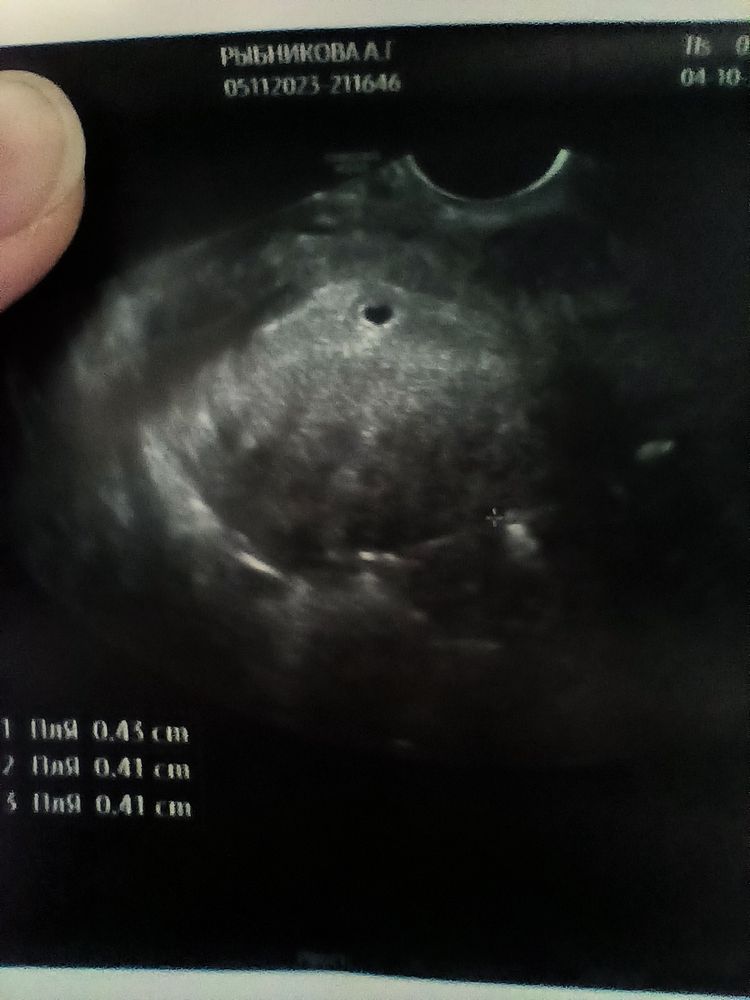

Вчера сходила на УЗИ, очень переживала по поводу внематочной и т.д. и т.п. Слава богу маточная, 4 недели 4 дня, плодное яйцо 4 мм, сказали придти через 10-15 дней чтобы услышать сердцебиение, надеюсь все будет хорошо 🌺 моя бусинка❤️❤️❤️